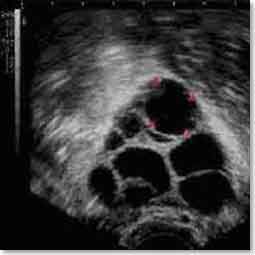

Doncs bé, la estimulació ovàrica prèvia a un tractament de FIV el que pretén és aconseguir que en comptes de que un sol òvul finalitzi el procés maduratiu, ho facin un nombre major que ens permeti donar expectatives d’embaràs a la dona, de forma ideal al voltant de la desena.

Això s’aconsegueix bàsicament elevant el nivell d’hormona FSH circulant, ja que com hem vist és el factor limitant en el moment de finalitzar la maduració ovocitària.